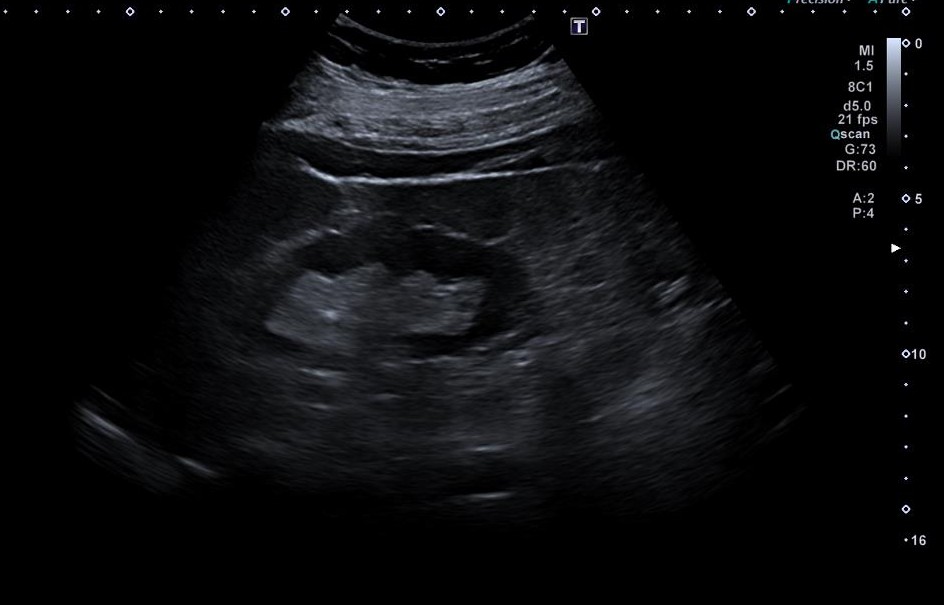

En consulta presenta dolor lumbar sin fiebre ni compromiso general. Se practica ecografía renovesical en la consulta, que muestra microlitiasis sin clara dilatación del sistema excretor, y una imagen anecoica bien delimitada y bilobulada, suprapúbica, en plano superior a vejiga de 1300 cc, Se realiza analítica urgente, objetivándose fracaso renal agudo, FRA, (FG 25 ml/min, Cr 2,06 mg/dl). Dado el FRA y hallazgo ecográfico se realiza derivación urgente a Nefrología.

En Urgencias, la ecografía muestra ligera dilatación pielocalicial derecha y presencia de imagen quística. El TC con contraste evidencia litiasis obstructiva distal de 7 mm con discreta dilatación ureteropiélica y una gran masa quística bilobulada dependiente de anexo derecho (150×124×134 mm), sin descartar componente sólido.